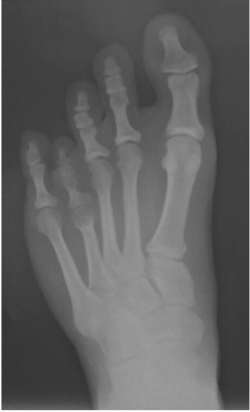

Brachymetatarsia, or hypoplastic metatarsal, is a rare condition characterized by an abnormally short metatarsal due to premature closure of the growth plate. According to the authors consulted, existing epidemiological data on the pathology are variable and its incidence is low, ranging between 0.02% and 0.05% (Jones, Pinegard, & Rincker, 2015; Urano & Kobayashi, 1978). Most cases of brachymetatarsia published in the literature correspond to cases of idiopathic congenital primary causes, although congenital cases associated with various diseases or syndromes have also been reported (Kim, Lee, Yoo, Kanq, & Suh, 2003). To a lesser extent, cases of brachymetatarsia, derived from trauma, tumors, infections, or iatrogenic conditions, have been reported (Kashuk, Hanft, Schabler, & Kopelman, 1991; Steedman & Peterson, 1992; Shim & Park, 2006). Existing studies coincide in highlighting a greater prevalence in females, although with a very varied relationship (Giannini, Faldini, Pagkrati, Miscione, & Luciani, 2010; Lee, Yang, Chung, Moon, & Jung, 2009; Trujillo Perez, Reina Bueno, Lafuente, & Munuera Martinez, 2007). Regarding the prevalence of bilaterality, there are also significant discrepancies, ranging between 36% and 72% (Barbier, Neretin, Journeau, & Popkov, 2015; Urano & Kobayashi, 1978). The fourth metatarsal was in all series the most affected (see Figures 1 and 2), followed by the first metatarsal.

Figure 2 - Click to enlarge in new windowFigure 2. Dorsoplanter radiograph of the patient's left foot. An abnormally short fourth metatarsal can be observed.